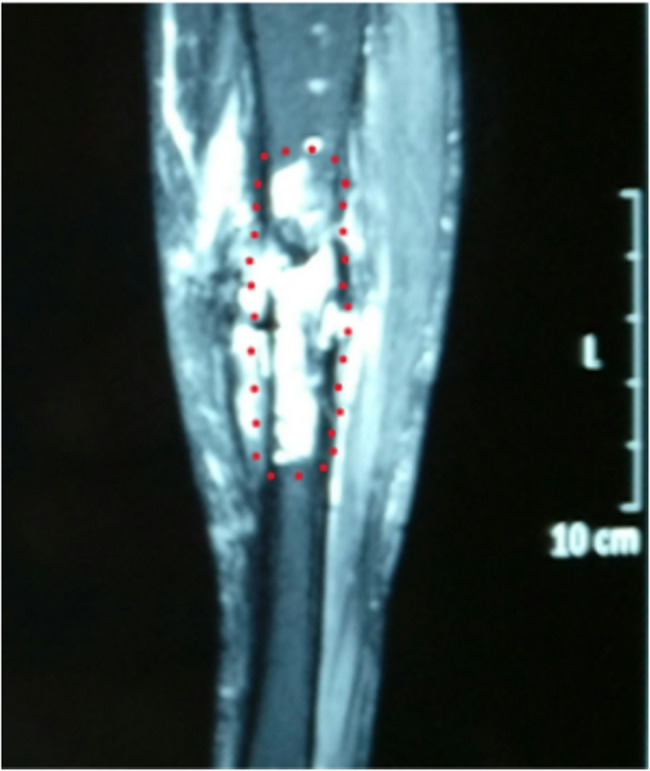

Methods: Seventy patients with Cierny-Mader stages III and IV chronic osteomyelitis admitted to the Department of Orthopedics of a Class III Grade A Hospital from January 2018 to March 2022 were selected for retrospective analysis and study. The following patient data were collected: gender, age, site of infection, bacterial culture results, internal fixation status, bone defect length, BMI, history of diabetes mellitus, smoking history, and history of preoperative antibiotic use. The patients were treated with sensitive antibiotics after surgery, followed up regularly, and venous blood C-reactive protein (CRP), sedimentation (ESR), white blood cells (WBC) and muscle strength (MTT scale), joint mobility (neutral 0° method), and bony healing time were measured to observe the recurrence rate of osteomyelitis and to assess the recovery of limb function according to the Enneking scale.

Results: Among the 70 patients, 20 cases were guided by X-ray, 30 cases by MRI, and 20 cases by SPECT. All patients underwent thorough debridement under the guidance of imaging modalities followed by external fixation. All cases were followed up and with a mean follow-up time of (12.2 ± 3.2) months. The recurrence rate of 35% in patients with X-ray as a guide was significantly higher than that of patients with MRI as a guide (10%) and SPECT as a guide (5%), and the difference between the three groups was statistically significant (P < 0.05).

Conclusion: For patients with osteomyelitis without metal internal fixation, the osteotomy surgical technique with MRI to guide the expansion of 0.5 cm distally and proximally, or with SPECT imaging to guide the surgical procedure in the area with 30-40% of the radioactive count contour (isocontour, ISO) had the advantages of low recurrence rate and good recovery of limb function, and the differences were not statistically significant. For patients with osteomyelitis with metal internal fixation, the osteotomy surgical technique with SPECT to guide the surgical procedure had the advantages of low recurrence rate and good recovery of limb function. In patients with osteomyelitis with metal internal fixation, SPECT was used as a guide to determine the extent of the osteomyelitis lesion, and osteotomy in the area with 30-40% of ISO was more effective than MRI.